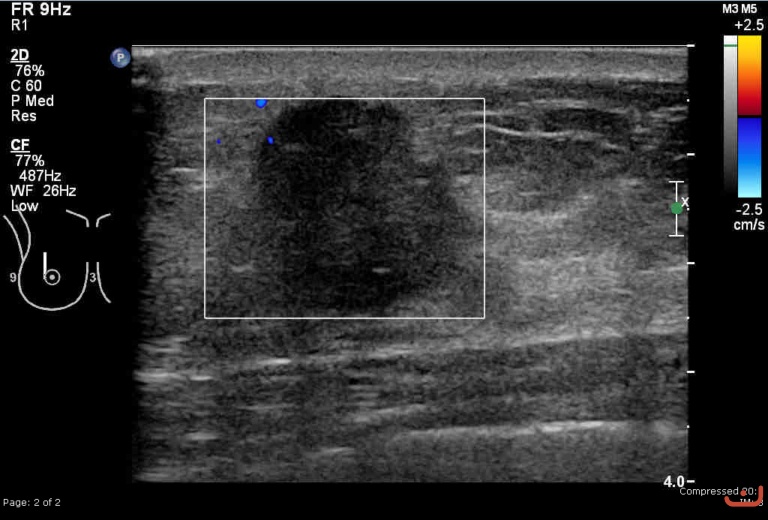

Malignant solid mass

Friday, 22 May 2015

203.84 KB (768 x 520 px)